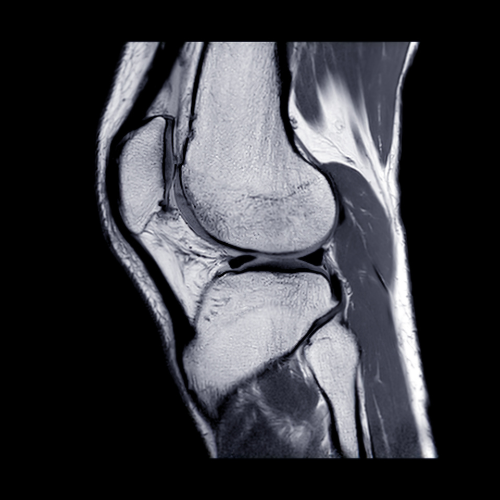

হাঁটুর লিগামেন্ট ইনজুরি (ACL, PCL, MCL, LCL injury)